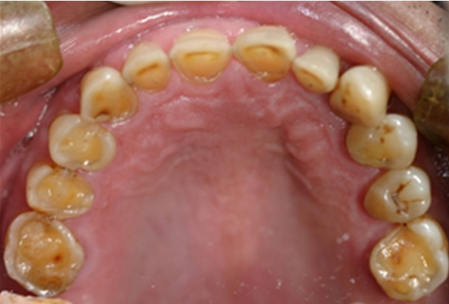

입안으로의 산 역류는 특히 치아 안쪽 표면의 에나멜질을 손상시킬 수 있다. 구강 건조, 입안의 산성 또는 작열감, 구취 및 입천장의 발적이 발생할 수 있다.[27] 위식도 역류병의 덜 흔한 증상으로는 연하 곤란, 물 넘어감, 만성 기침, 쉰 목소리, 메스꺼움 및 구토가 있다.[26]

에나멜질 부식의 징후는 페리키마가 없는 매끄럽고 비단결같이 광택이 나며 때로는 둔탁한 에나멜 표면이 잇몸 경계를 따라 온전한 에나멜과 함께 나타나는 것이다.[28] 수복물이 있는 사람의 경우, 치아 구조가 일반적으로 수복 재료보다 훨씬 빠르게 용해되어 주변 치아 구조보다 "위로 솟아" 보이는 것처럼 보이게 된다.[29]